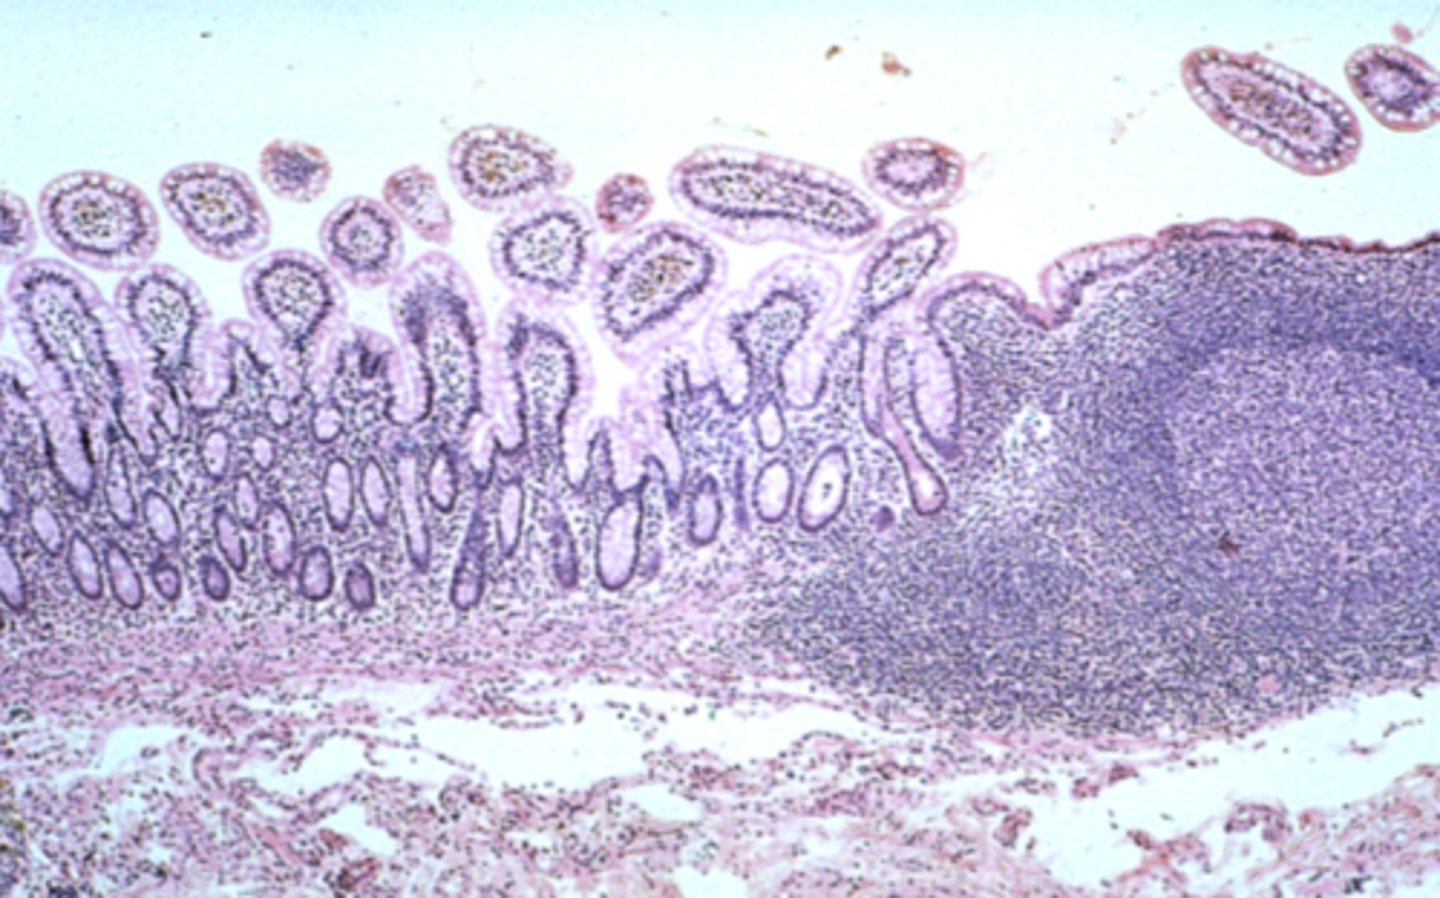

ileum

What is this?

ileum Peyer's patch

What is this?

jejunum

What is this?

Jejunum has no Brunner's gland or malt tissue

duodenum and ileum vs jejunum